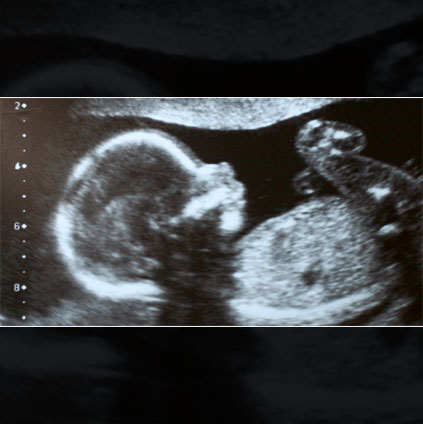

Ultrasound image from TIFFA scan showing fetal anatomy used to detect congenital abnormalities and monitor baby’s development during pregnancy

A TIFFA Scan (Targeted Imaging For Fetal Anomalies) Scan is popularly known as Fetal Anomaly Scan. It is one of the most important scans conducted during pregnancy because it detects any congenital abnormalities in the growing fetus. This scan is done between 18 - 22 weeks of pregnancy. In this scan, the baby is screened from head to toe to look for abnormalities. It can be a 3-dimensional or 4-dimensional scan (3D or 4D scan).